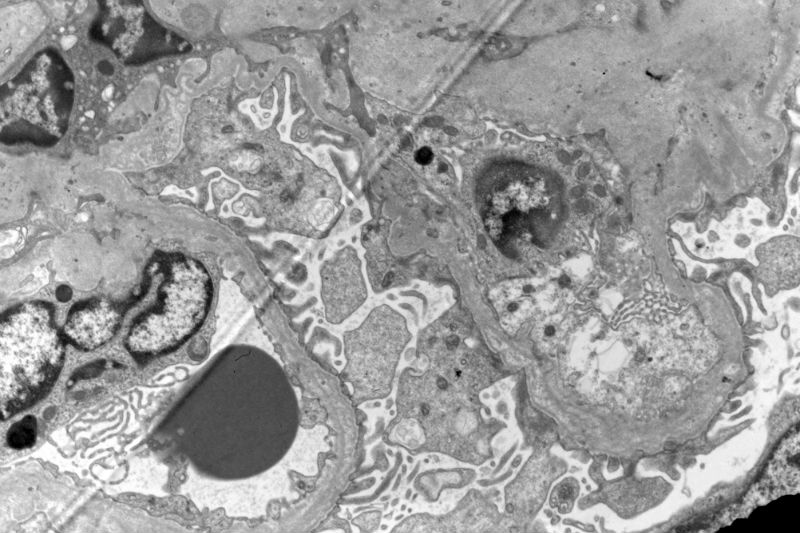

The patient has a long history of "chronic kidney disease". Initially, he did not tell the nephrologist that he started to have kidney disease decades ago. Given the characteristic ultrastructural changes, Alport's syndrome is suggested.

Yes, I agree with your observation that there are a lot of foamy cells. The most impressive change is the lamination or splitting of the glomerular basement membrane.